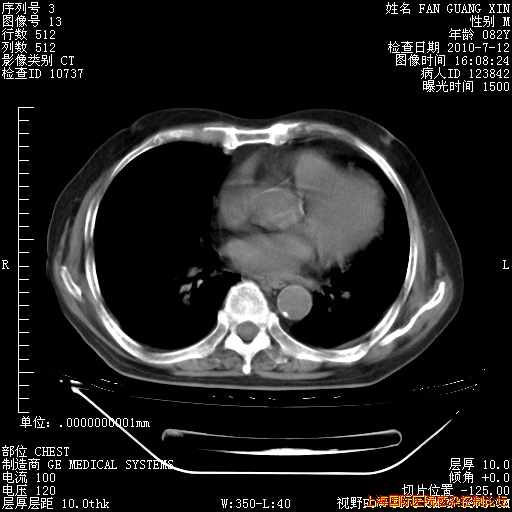

6月12日纵膈窗

回复

整整相隔30天的肺部CT好像有所好转啊。甲强龙减量第3天,需要观察体温。

海管,自昨日你和我通完话后,不知您岳父消化道症状有无缓解?体温怎样?阅读7.12日胸部ct,个人认为目前激素治疗是有效的,甲强龙减量是适宜的。因在抗痨治疗,需密切观察肝功、肾功能和血常规。不过,老年、长期住院和大量使用激素,很担心菌群失调发生